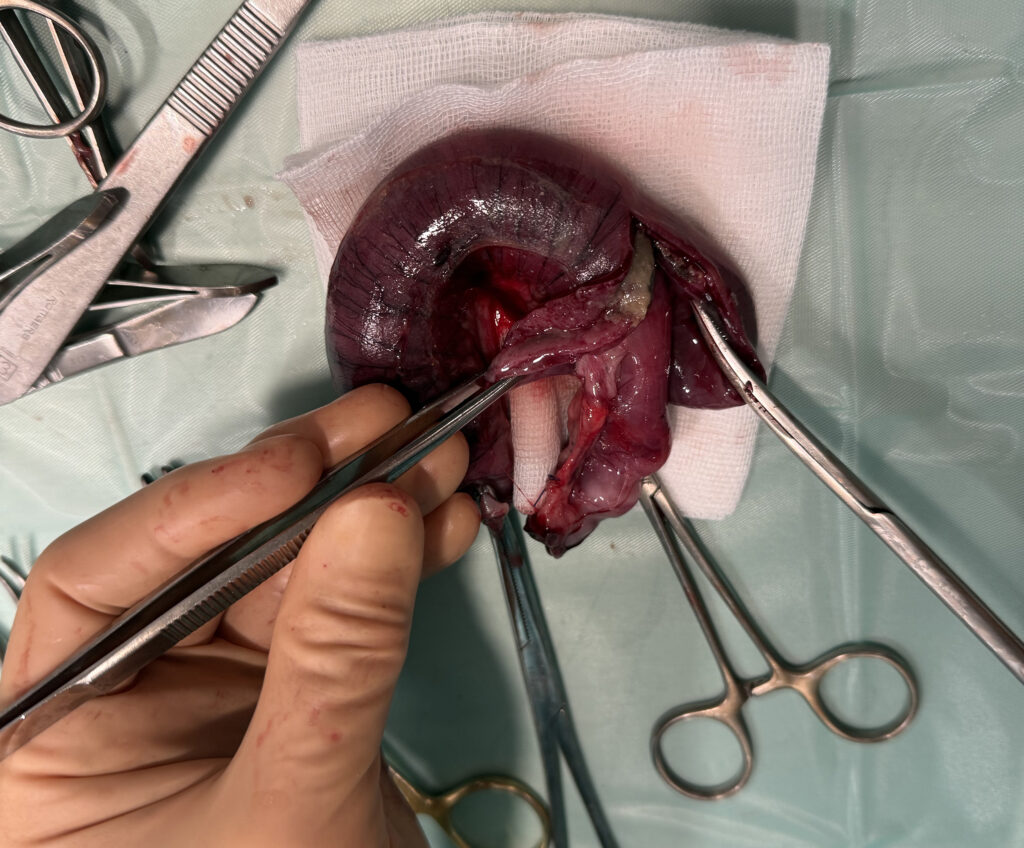

De enige afdoende oplossing voor een darminvaginatie is via een operatie de darm weer uit elkaar te schuiven. Doordat de darm gedeeltelijk afgesloten kan zijn, met eventueel al deels afsterven tot gevolg, kan het nodig zijn een stuk darm te verwijderen. Gelukkig kan een dier hier goed mee leven. Aanvullend moet een hond of kat ondersteund worden met infuus, antibiotica en maag-darmmedicatie tijdens en na de operatie.